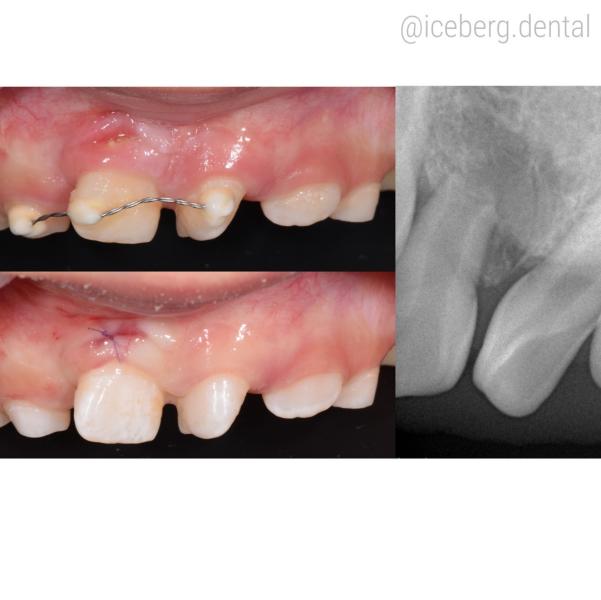

Провели удаление резца 11, который находился внутри челюсти и располагался «вверх ногами» (положили в физ.раствор — время 10-15 мин) и далее удалили сверхкомплектные зубы, сформировали лунку и поместили удаленный зуб на место в правильном положении. Затем зафиксировали шиной.

Через 7 дней сняли швы, через месяц сняли шину.